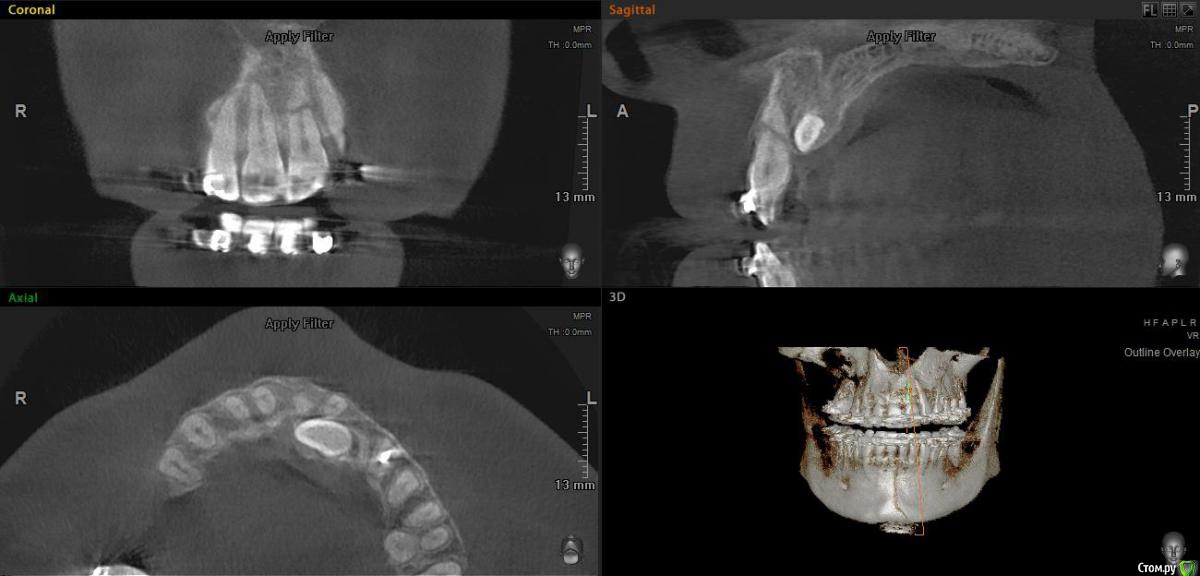

elen_only Опубликовано 10 февраля, 2020 Поделиться Опубликовано 10 февраля, 2020 Доброго дня всем,коллеги! Всех с прошедшим Днём стоматолога! Открыла тему в терапии и здесь продублирую. Ситуация такая:направил ко мне ортодонт на резекцию верхушки корня молодого мужчину. В анамнезе травма передних зубов,лет 10 назад. Год назад поставили брекет-систему. Иногда жалуется на небольшую болезненность при накусывании. Зуб подвижен,в цвете не изменён. Прикрепляю снимки,разница между первым и вторым-год. Доктор не заметила перелом корня зуба 21 и поставила брекеты. Удалить зуб и вкрутить сразу имплантат (как хотелось бы) не получится,у пациента ретинированный клык,который будут пытаться вытянуть. В связи с этим вопрос: как сохранить этот зуб,хотя бы до момента ,когда вытянут клык? Думала запломбировать верхнюю часть и удалить верхушку,но в общем-то за год никаких периапикальных изменений не появилось,кроме резорбции отломков,может и не трогать. Как правильнее поступить?1.запломбировать верхнюю часть,не трогать верхушку2. Запломбировать верхнюю часть и удалить верхушку3. Вообще не трогать зуб,сколько постоит.И если пломбировать,то чем? И как мыть эту часть гипохлоритом,чтобы не вышел куда не надо? Вдруг,кто сталкивался с таким Ссылка на комментарий

elen_only Опубликовано 10 февраля, 2020 Автор Поделиться Опубликовано 10 февраля, 2020 (изменено) Коллега, я вам на всякий случай напишу мой протокол работы с горизонтальными переломами. 1. Определить витальность зуба. Зуб витален - оставляем, наблюдаем. 2 нед., 1 месяц., 2 мес., 6 мес., год. А там уже мостик сформируется. Если подвижен, временная шина.2. Зуб невитален - эндо коронкового фрагмента. Наблюдаем.3. Безуспешно - удаляем апикальную часть по типу РВК. Ретроградная пломбировка коронкового фрагмента.4. Безуспешно - удаляем. Вы поплыли на первом пункте, извините. Если бы мы говорили о какой-то четвёрке, то может игра свеч не стоит. Но мы говорим о переднем зубе. Здесь куча сложностей и осложнений могут быть. У вас ещё и клык притаился. Успехов!Так я же и написала,что зуб год под брекет-системой. Снимки разницей в год. Жалоб не было. Подвижность была с момента травмы,около 10 лет. Периапикальных изменений за год нет. Болезненность появляется, когда ортодонт даёт тягу,уж не знаю,как это правильно называется. Без ортодонтическом лечения,зуб вообще бы не трогали. А так вопрос,что делать Изменено 10 февраля, 2020 пользователем elen_only Ссылка на комментарий

Astronaft Опубликовано 12 февраля, 2020 Поделиться Опубликовано 12 февраля, 2020 (изменено) http://miworks.weebly.com/uploads/1/6/8/7/16879370/9508255_orig.jpg http://miworks.weebly.com/uploads/1/6/8/7/16879370/2163396_orig.jpg У меня есть такой пациент. Зуб витальный, наблюдал около 3 лет. Сначала зашинировал, потом все снял. Все в порядке, кроме повышенной подвижности.Не спешите списывать зуб. У природы огромные силы к восстановлению. Изменено 12 февраля, 2020 пользователем Astronaft Ссылка на комментарий